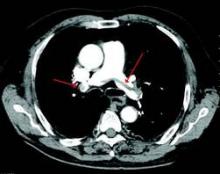

A large pulmonary embolism at the bifurcation of the pulmonary artery (saddle embolism). Courtesy Dr. James Heilman

A large pulmonary embolism at the bifurcation of the pulmonary artery (saddle embolism).